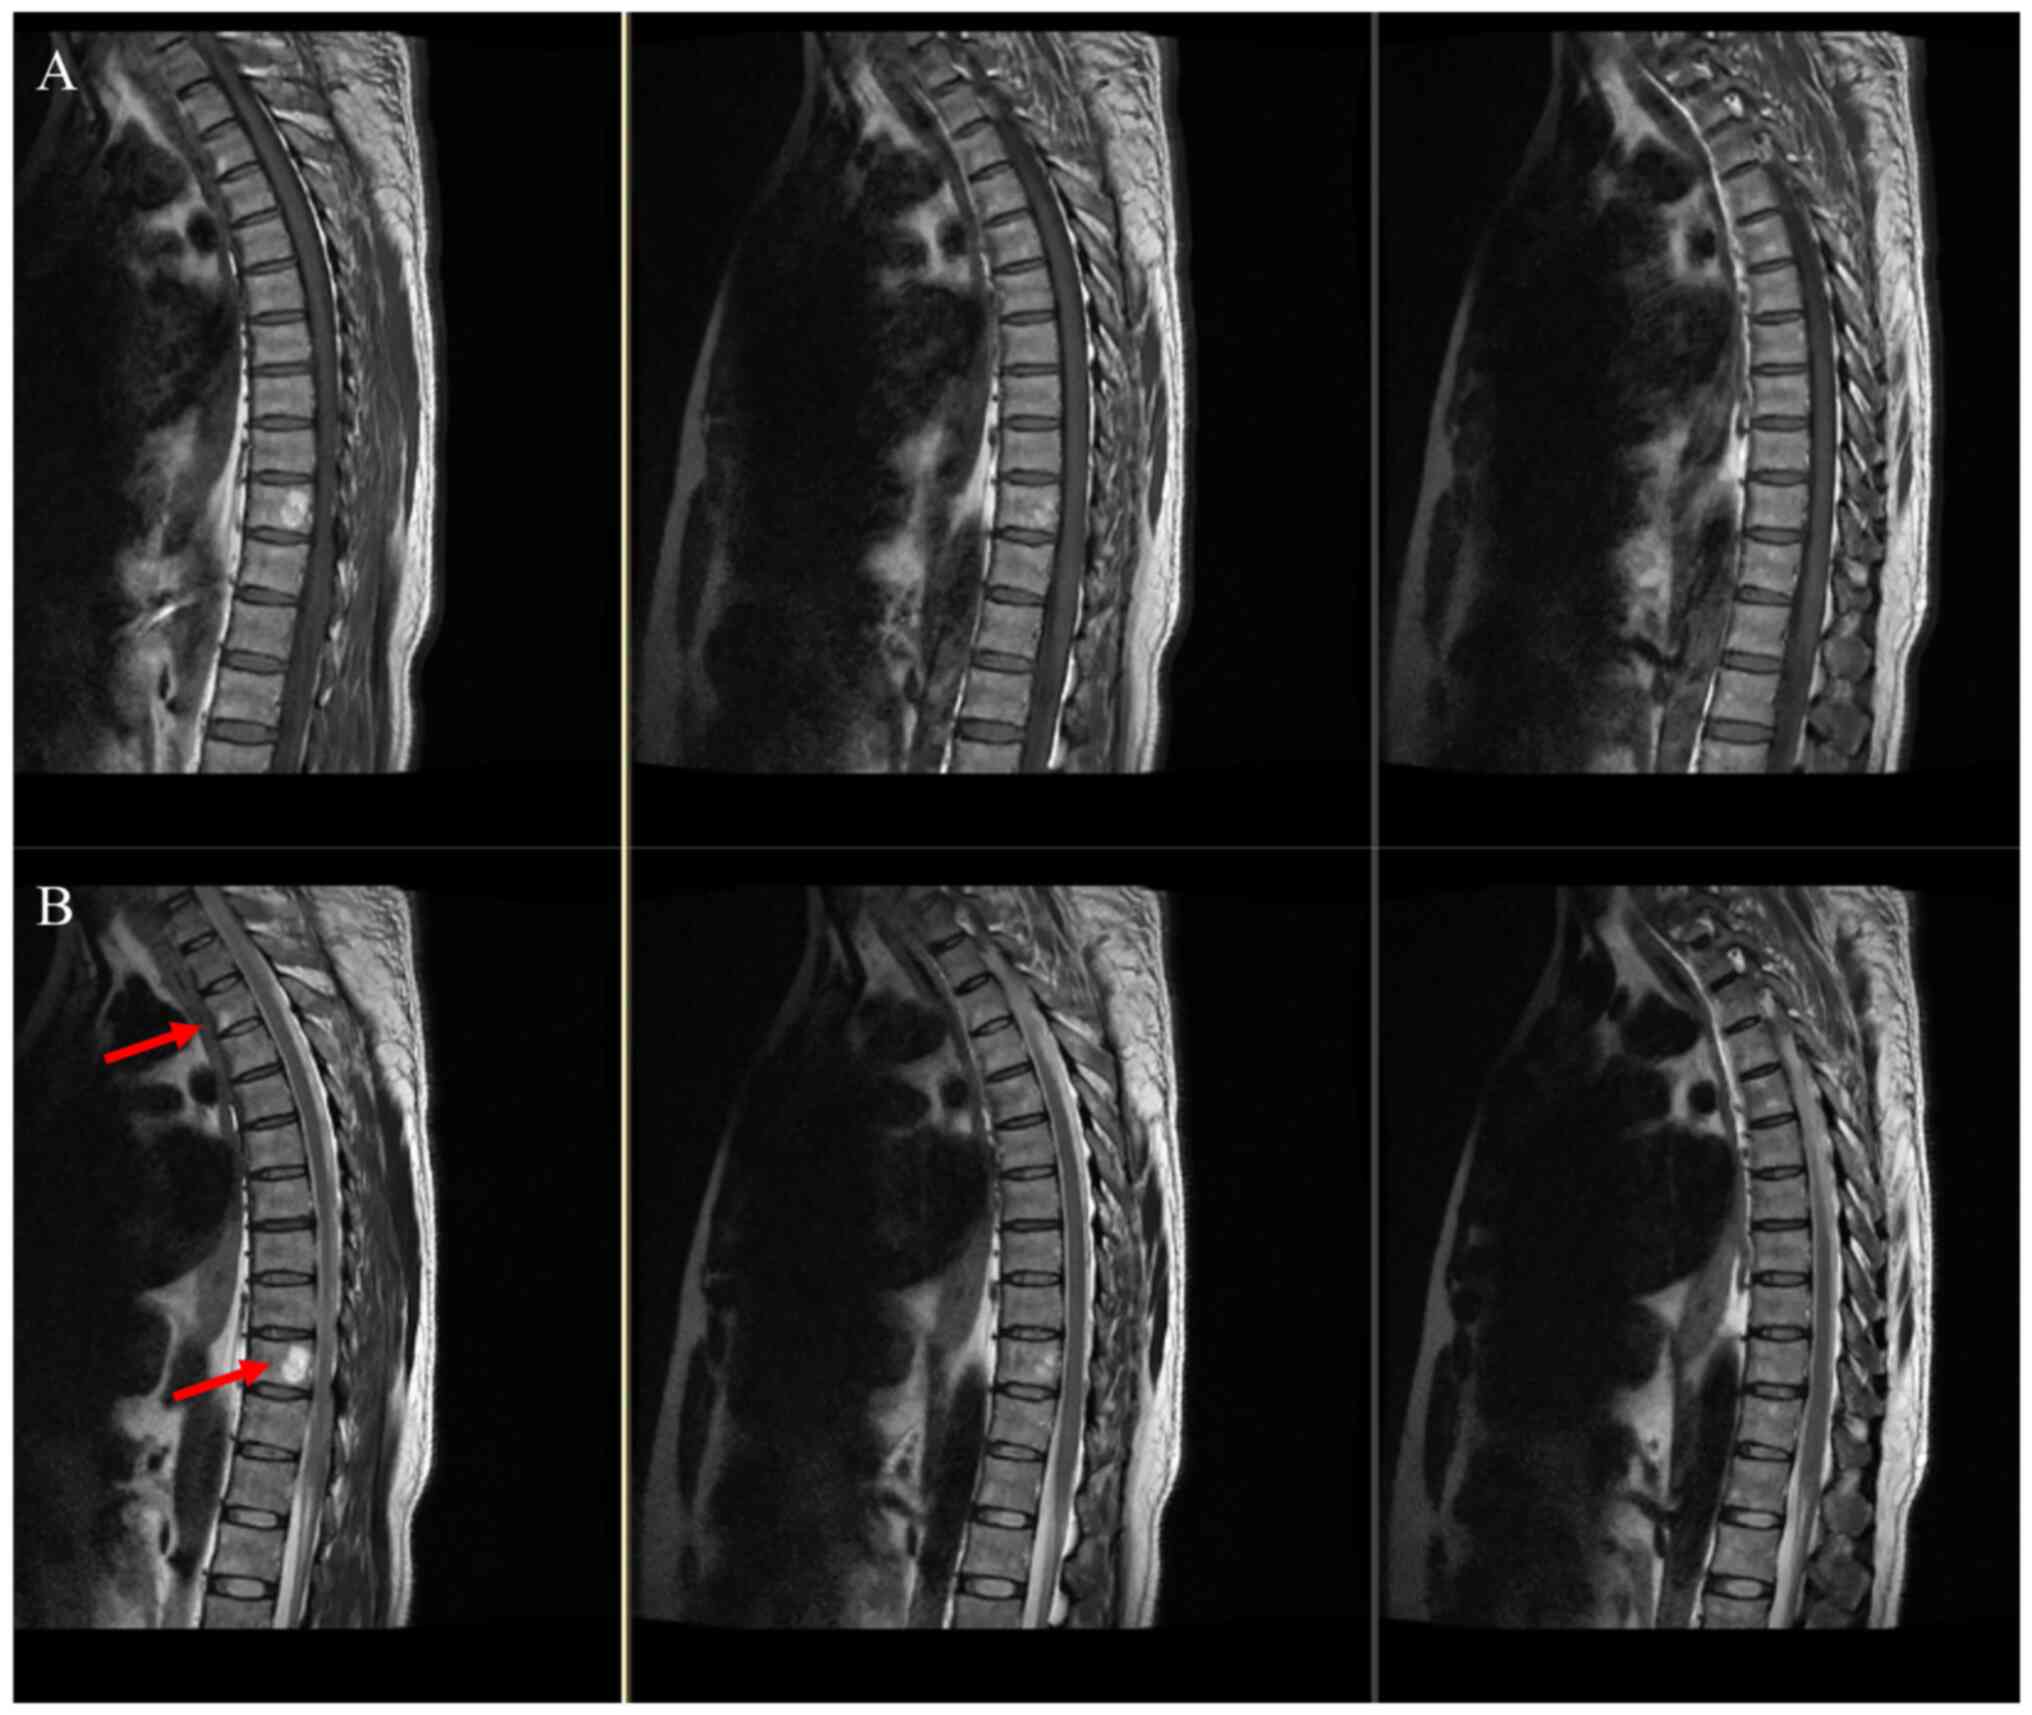

Weighted MRI of the patient's thoracic spine 5 days after the surgery. (A) T1-weighted and (B) T2-weighted MRI images. T3 and T10 vertebral hemangiomas were suspected, as indicated by the red arrow. MRI, magnetic resonance imaging.

Figure 5

Weighted MRI of the patient's lumbosacral spine 4 days after the surgery. (A) T1-weighted and (B) T2-weighted MRI images. The lumbosacral spine MRI scan indicated a slight hematoma in the subarachnoid space below the L2 level, as indicated by the red arrow. MRI, magnetic resonance imaging.